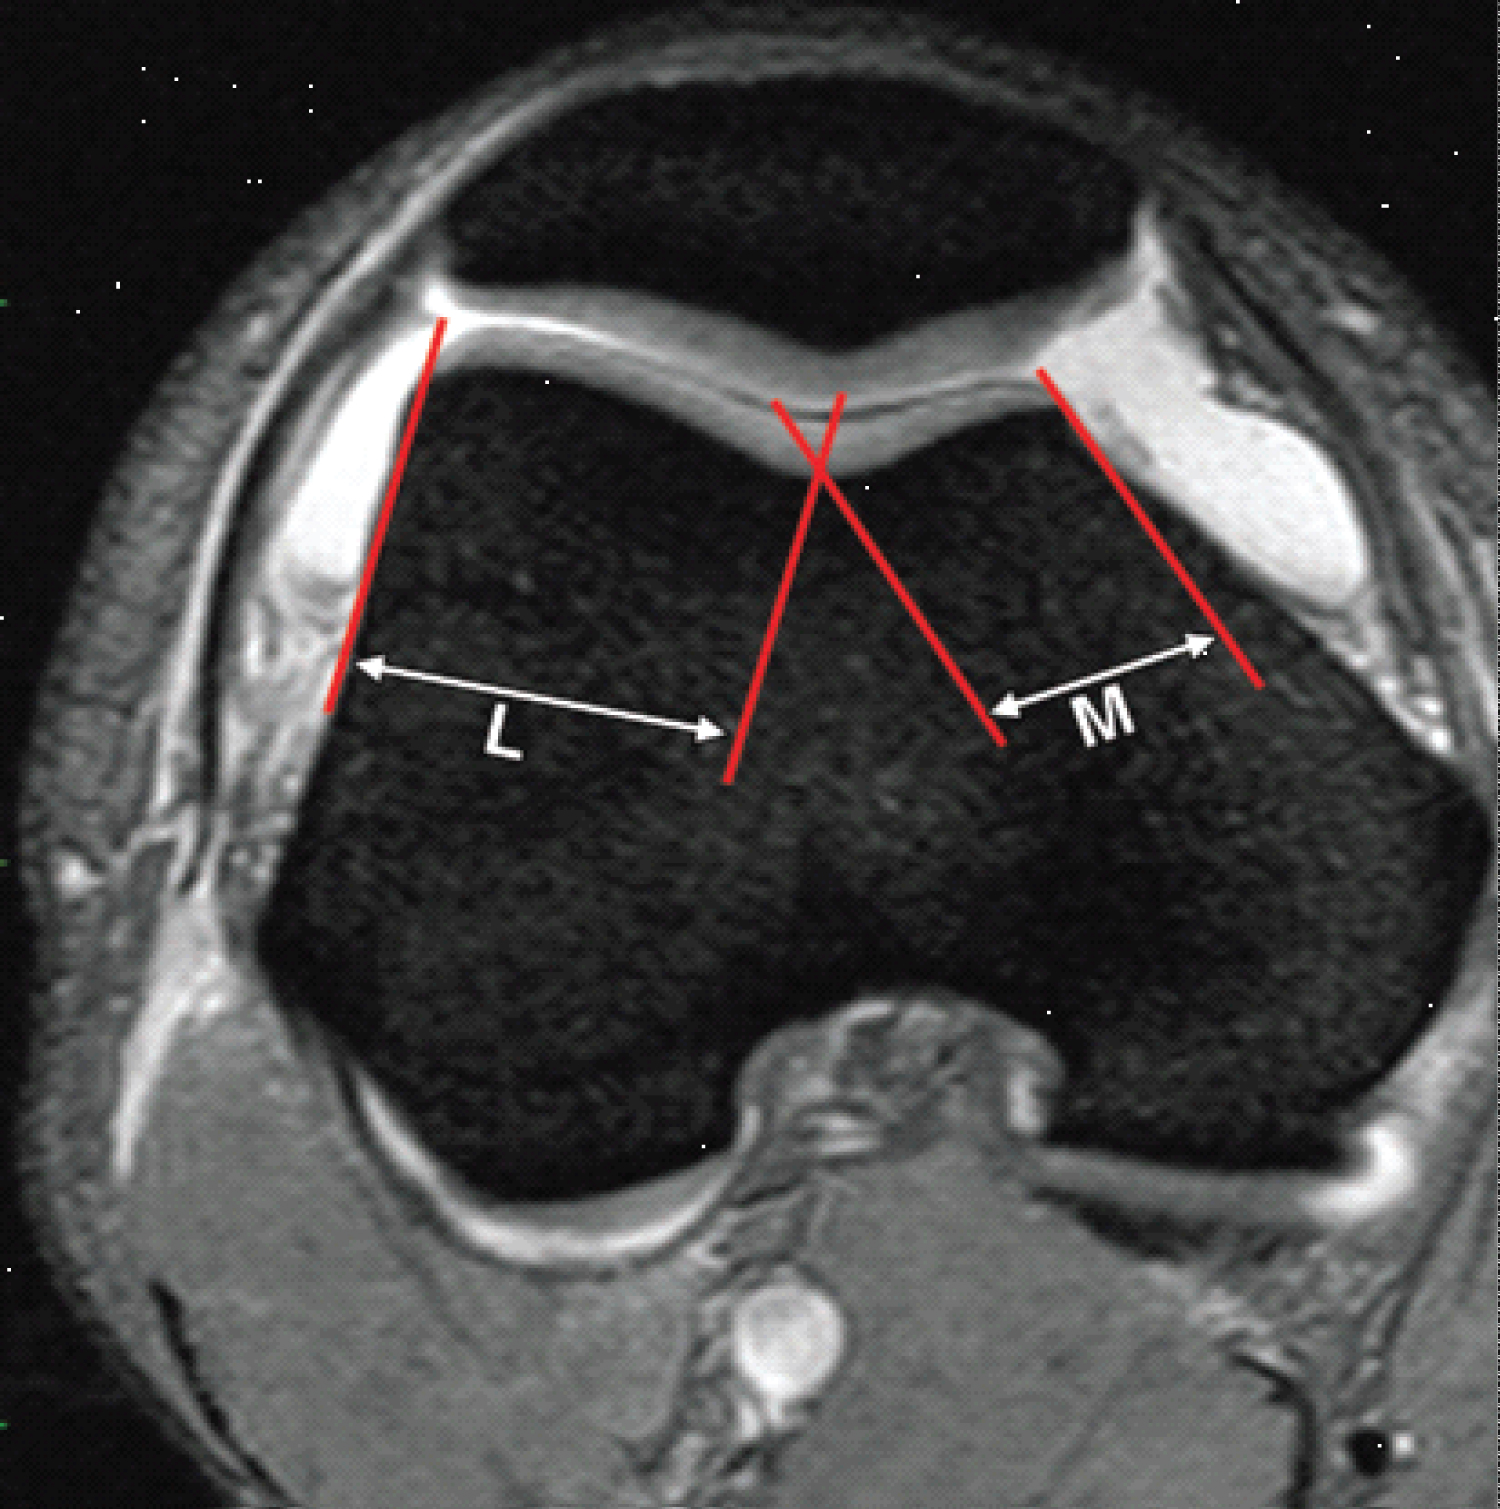

b) Trochlear facet asymmetry, MRI slices at about 3 cm above the tibiofemoral joint space were use. Trochlear facet asymmetry was expressed with the relation of medial trochlear facet width (e) to lateral trochlear facet width e/f × 100%. A ratio of less than 0.4 is considered abnormal which means that the medial facet is less than 40% the width of the lateral one (Figure 4) [6].

Figure 4: Trochlear facet asymmetry assessed on axial fat-saturated T2-weighted MR images. Asymmetry of the medial facet length (M) and the lateral facet length (L) is calculated as the ratio of the medial facet length divided by the lateral facet length expressed as a percentage (M/L × 100%). A trochlear facet ratio of less than 40% indicates dysplasia. View Figure 4